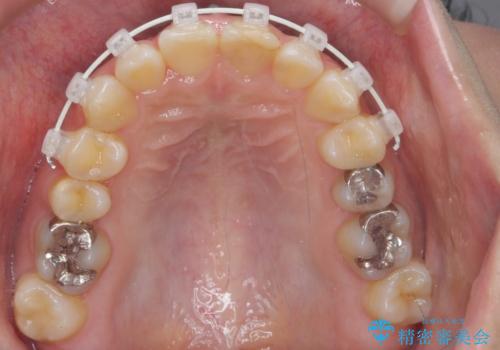

前歯のがたつき ガミースマイルの改善

上の前歯をひっぱりあげて目立たなくするために、上の前歯のワイヤー部分矯正を行い、ミニスクリューからわずかに引っ張り上げました。

また、右上の犬歯の反対咬合についてもワイヤー矯正で短期間で改善することができました。

前歯の過蓋咬合についても改善しています。

前歯(犬歯)の反対咬合は改善はインビザラインですと時間がかかるため、ワイヤー矯正で短期間で入れ替えるほうが、患者様の負担が少なくて済みます。

入れ替える期間は前歯しか当たらない状態になり、大変食事もしにくくなるうえ、前歯にも負担がかかります。ワイヤーは少々目立ちますがおすすめです。